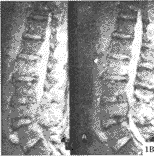

2.2 脊柱转移癌的MRI特点 骨髓被转移癌浸润导致T1驰豫时间延长及相应T1像信号强度的降低,转移癌表现为局灶性或弥漫性低信号,区别于T1加权像高信号的正常骨髓背景(图1A)。大多数转移癌T2加权像呈高信号(图1B)。钆-DTPA缩短T1弛豫时间,在T1加权像增强扫描,使骨病损信号增强,可以帮助鉴别那些诊断困难的脊柱转移癌。

图1 MRI

T1像(A)T10、L2及L4椎体弥漫性低信号,且L1,3,5椎体局灶性低信号;T2像(B)T10、L2及L4弥漫性高信号,部分椎体相当于T1像的部位局灶性高信号